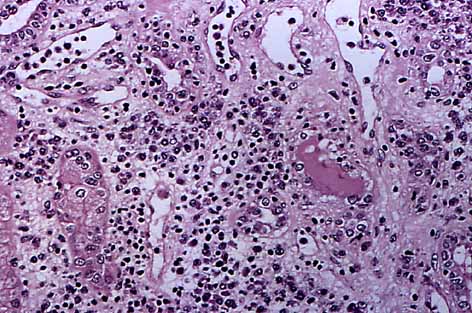

Histopatológicamente es importante demostrar una íntima relación entre dicho componente linfocitario y el epitelio tubular, fenómenos que se denomina emperipolesis y/o "túbulitis" (21). Para una mejor visualización de este fenómeno, es muy útil la tinción de PAS que delimitará con claridad la membrana basal de los túbulos y así permitirá el contaje de linfocitos permeabilizando el epitelio tubular (fig. 4).

| Figura 4. Denso infiltrado inflamatorio linfocitario con destrucción del epitelio tubular y edema (tubulitis). |

El infiltrado inflamatorio túbulo intersticial y la tubulitis, es altamente sensible para un diagnóstico de RATI, pero no siempre que exista nefritis intersticial linfocitaria debemos de hace el diagnóstico de RATI, pudiéndo existir cuadros imitadores generalmente secundarios a infeccion vírica por CMV (15).

Es muy importante la aplicación de los criterios de Banff no solo para el diagnóstico sino también para graduar la intensidad del rechazo. Basándonos en dichos crierios, es necesario la presencia de infiltrado inflamatorio linfocitario, destrucción de membrana basal tubular y tubulitis (24).